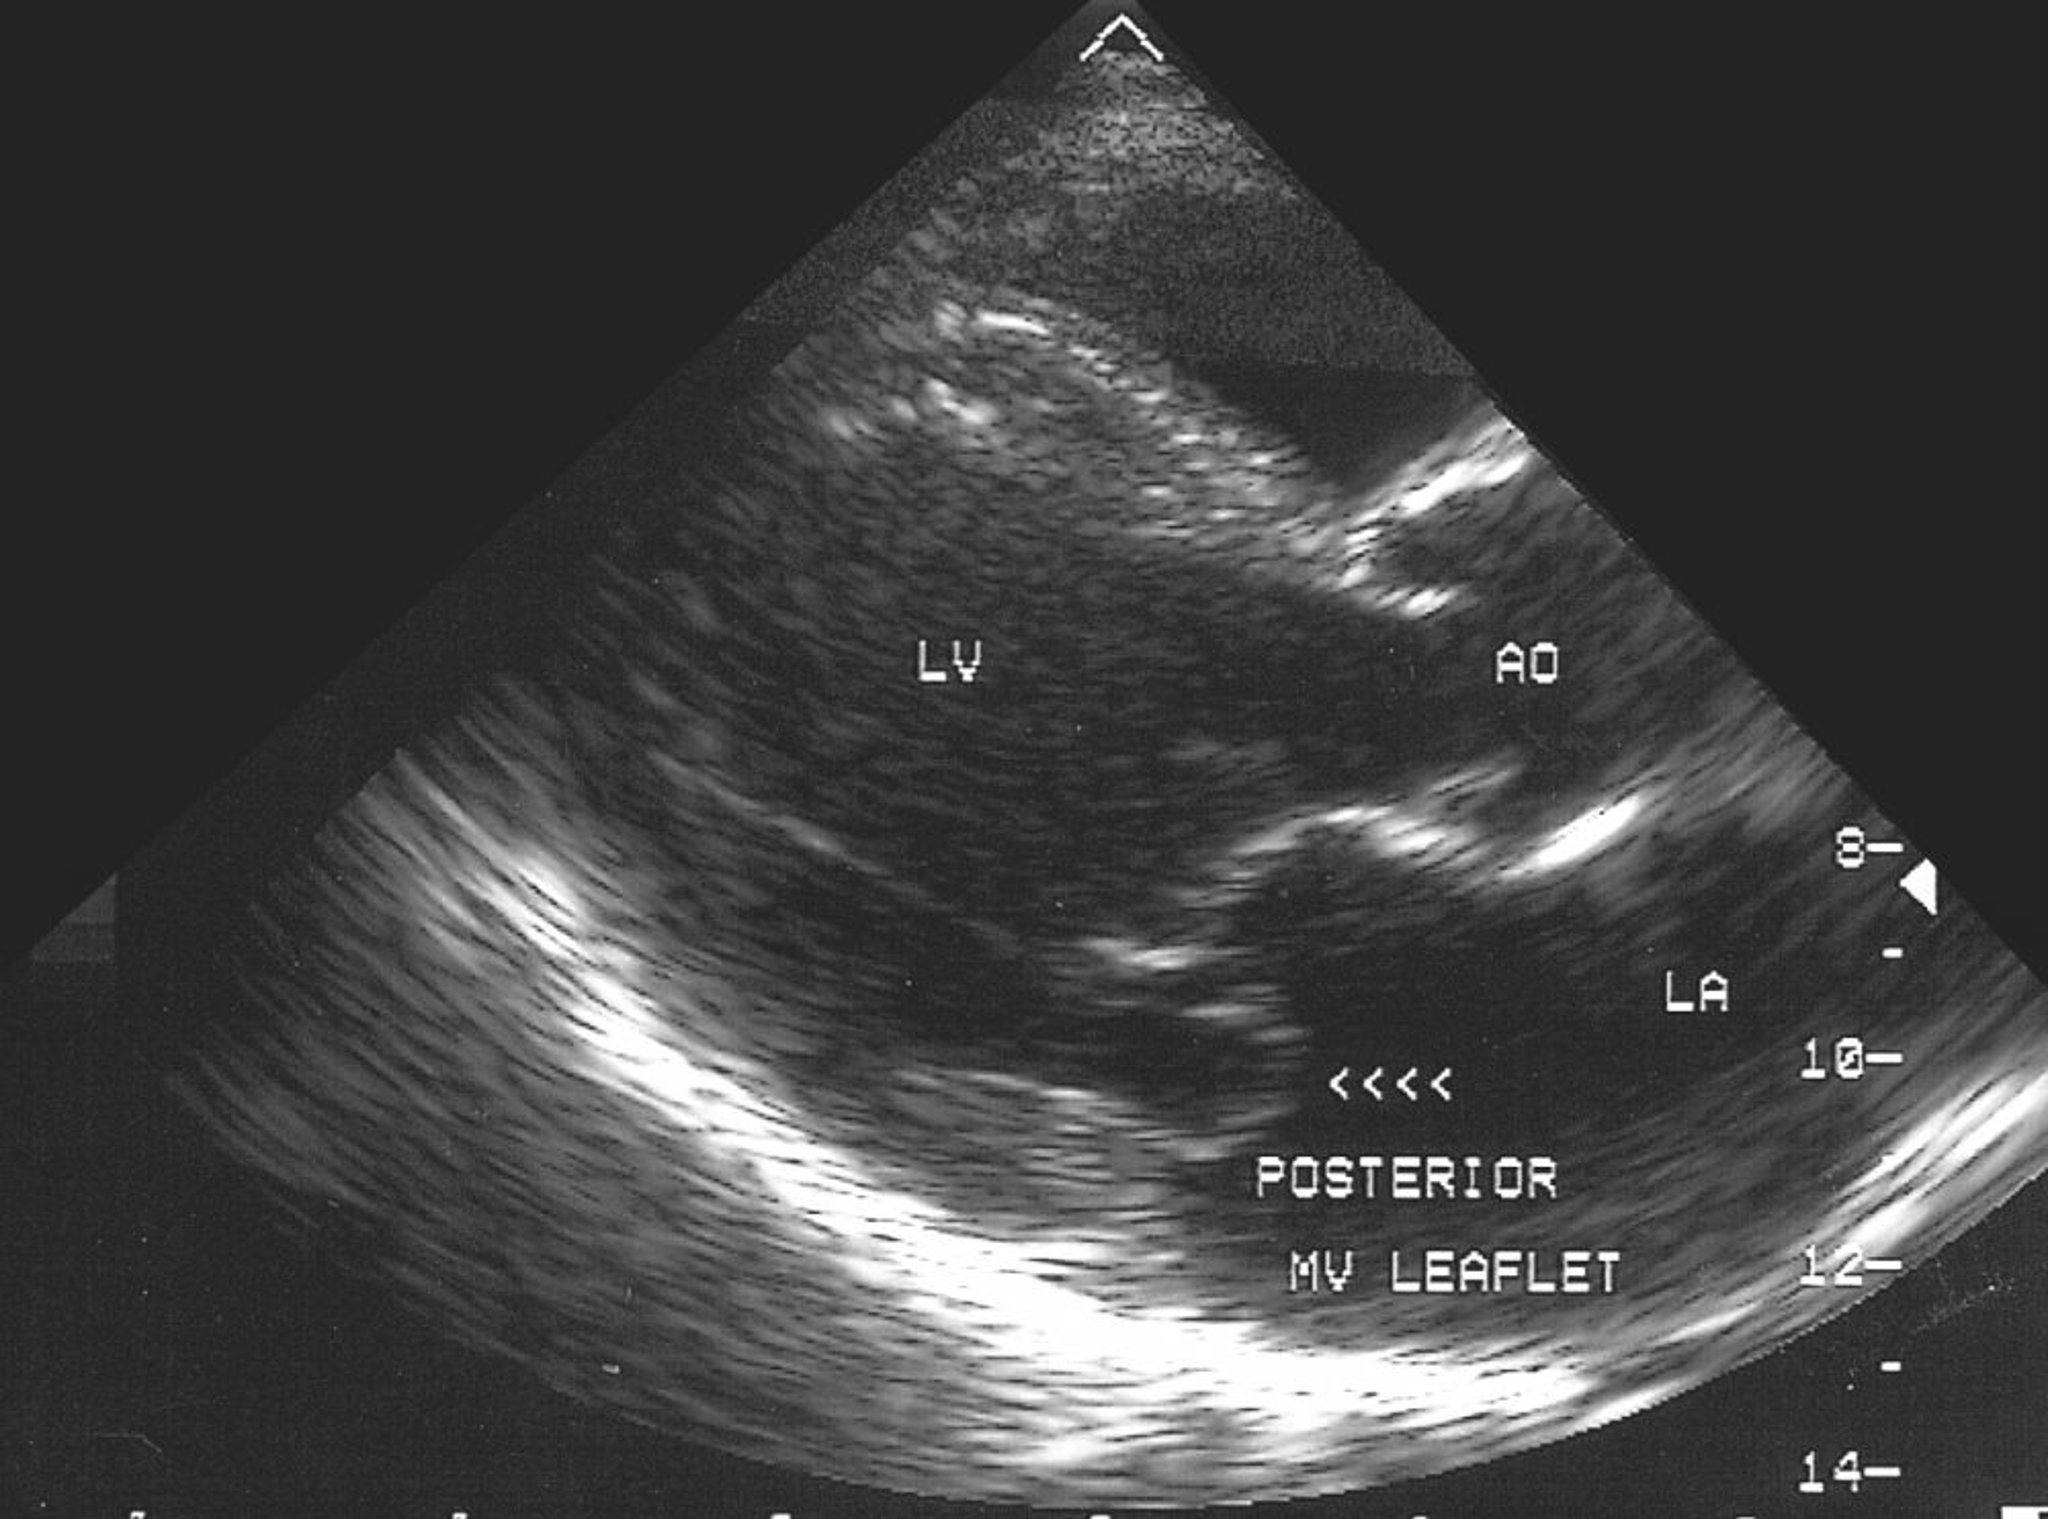

Prolapso da valva mitral (ecocardiograma)

Essa imagem ecocardiográfica mostra prolapso da folheto posterior da valva mitral no átrio esquerdo (AE).